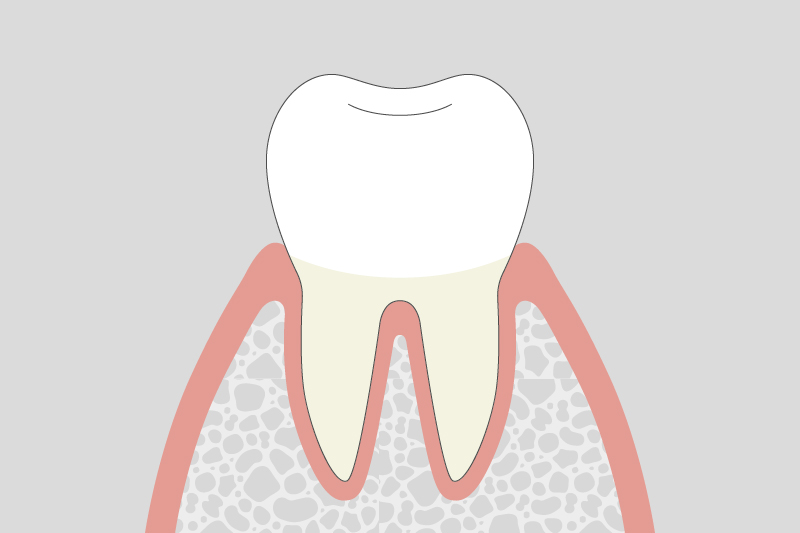

歯周病治療について

歯周病は、自覚症状が少ないまま進行することが多く、気づいた時には症状が進んでいる場合もございます。歯周病の進行を食い止め、大切な歯を健康に保ち続けるために、当院がどのように歯周病治療に取り組んでいるのかをご紹介いたします。

歯周病治療とは

歯周病は、一度かかってしまうと完全に元に戻るのが難しい、生活習慣に関わる慢性的な病気です。そのため、一時的に治療をして終わりではなく、病気の進行を抑え、今の良い状態を長く保っていくことが何よりも大切になります。